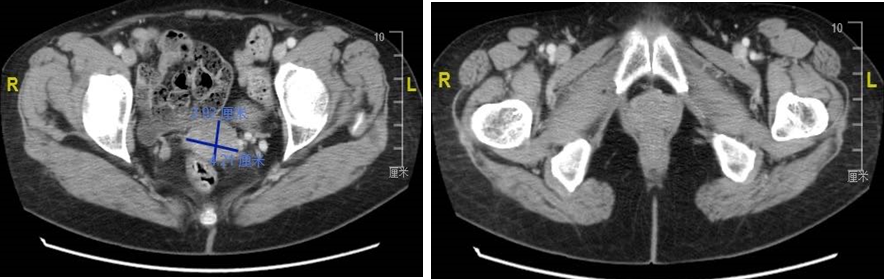

CT检查:宫颈见不均匀强化肿块影,约2.92*4.21cm,阴道后壁肿块约4.56*4.35cm,病灶与宫颈后唇分界不清。

图1. CT提示宫颈占位,见不均匀强化肿块影,约2.92*4.21cm,阴道后壁肿块约4.56*4.35cm,病灶与宫颈后唇分界不清。颈、胸部未见异常

PET-CT检查:阴道全程壁增厚,FDG代谢增高,病灶累及宫颈,与直肠及膀胱前壁分界不清,考虑肿瘤复发可能大,病灶侵犯直肠及膀胱可能。

图4. PET-CT提示阴道后壁肿瘤复发,SUV值高,病灶与直肠及膀胱前壁分界不清,考虑病灶侵犯直肠及膀胱可能,另有可疑转移灶